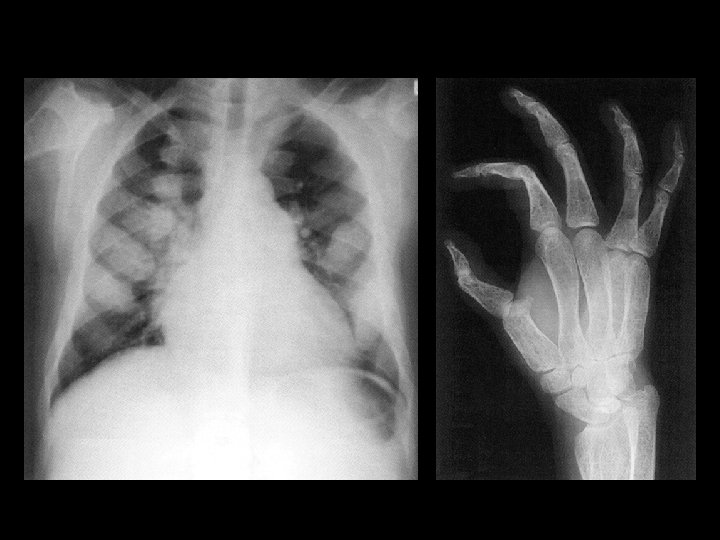

Thalassemia Major